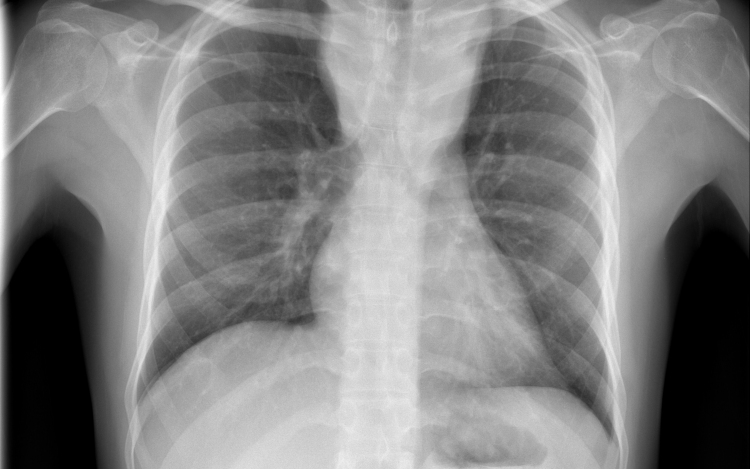

Csökkent a tbc-fertőzések száma Európában

Átlagosan 4,3 százalékkal csökkent az új tuberkulózisos (tbc-s) esetek száma 2010 és 2014 között az Egészségügyi Világszervezet (WHO) 53 országot magába foglaló európai régiójában.

A becslések szerint 2014-ben 340 ezer európai betegedett meg tuberkulózisban, ami százezer emberre vetítve 37 esetnek felel meg. Azzal, hogy 2010 és 2014 között átlagosan 4,3 százalékkal csökkent az új esetek száma, az európai régió teljesítette azt a millenniumi fejlesztési célt, hogy 2015-re visszafordítja a tbc terjedésének tendenciáját.

Magyarországon biztonságos a tbc-re vonatkozó epidemiológiai helyzet: 2014-ben nyolc új eset jutott százezer lakosra, és az előzetes adatok szerint ugyanez igaz a 2015-ös évre is. Így a WHO Magyarországot az alacsonyan átfertőzött országok között tartja nyilván. Alacsony a multirezisztens esetek száma - 2014-ben hét új esetet észleltek -, valamint a gyermekkori megbetegedéseké is: 2014-ben hat 14 éven aluli gyermek betegedett meg.